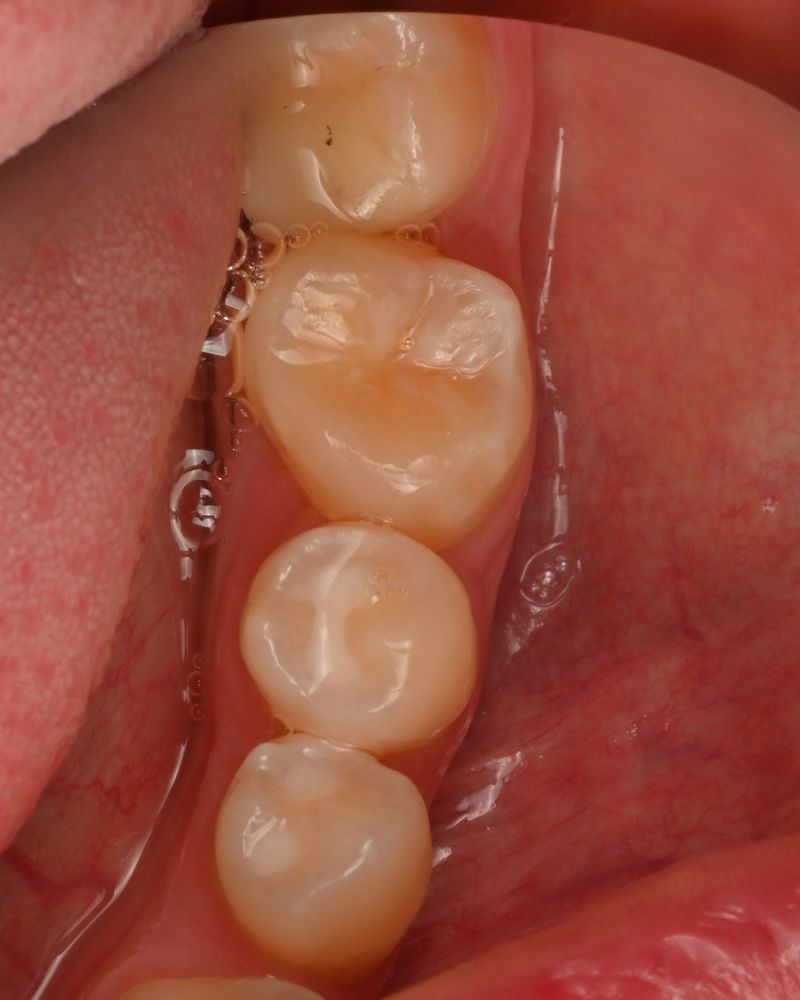

После подготовки мы пересадили зуб мудрости и зафиксировали его тонкой шиной.

Через 20 дней шину сняли — зуб хорошо прижился. Спустя два месяца он уже полноценно участвовал в жевании, а снимки показывали стабильную и правильную адаптацию.